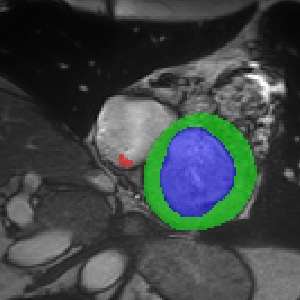

Transformers, the default model of choices in natural language processing, have drawn scant attention from the medical imaging community. Given the ability to exploit long-term dependencies, transformers are promising to help atypical convolutional neural networks (convnets) to overcome its inherent shortcomings of spatial inductive bias. However, most of recently proposed transformer-based segmentation approaches simply treated transformers as assisted modules to help encode global context into convolutional representations without investigating how to optimally combine self-attention (i.e., the core of transformers) with convolution. To address this issue, in this paper, we introduce nnFormer (i.e., Not-aNother transFormer), a powerful segmentation model with an interleaved architecture based on empirical combination of self-attention and convolution. In practice, nnFormer learns volumetric representations from 3D local volumes. Compared to the naive voxel-level self-attention implementation, such volume-based operations help to reduce the computational complexity by approximate 98% and 99.5% on Synapse and ACDC datasets, respectively. In comparison to prior-art network configurations, nnFormer achieves tremendous improvements over previous transformer-based methods on two commonly used datasets Synapse and ACDC. For instance, nnFormer outperforms Swin-UNet by over 7 percents on Synapse. Even when compared to nnUNet, currently the best performing fully-convolutional medical segmentation network, nnFormer still provides slightly better performance on Synapse and ACDC.